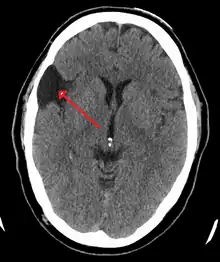

A CT scan of an arachnoid cyst

The diagnostic process typically begins with a medical history workup followed by a medical examination by a physician. Imaging tests, such as CT scans and MRIs, help provide a clearer picture. The physician typically looks for fluid (or other bodily substance) filled sacs to appear in the scans, as is shown in the CT scan of a colloid cyst. A primary health care provider will refer an individual to a neurologist or neurosurgeon for further examination. Other diagnostic methods include radiological examinations and macroscopic examinations. After a diagnosis has been made, immunohistochemistry may be used to differentiate between epithelial cysts and arachnoid cysts.[2] These examinations are useful to get a general idea of possible treatment options, but can be unsatisfactory to diagnose CNS cysts.[3][5] Professionals still do not fully understand how cysts form; however, analyzing the walls of different cyst types, using electron microscopes and light microscopes, has proven to be the best diagnostic tool. This has led to more accurate cyst classification and correct course of action for treatments that are cyst specific. In the past, before imaging scans or tests were available, medical professionals could only diagnose cysts via exploratory surgery.[2]